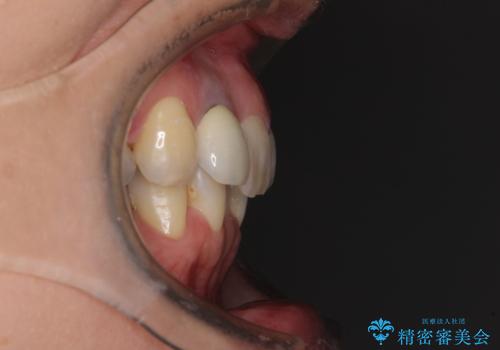

左上前から2番目の歯は、以前裏側に位置していたことから抜歯をされていましたが、前歯の非対称が長年気になっているとのことでした。

矯正治療によって前歯にスペースを作り、左右対称となるようにオールセラミッククラウンにて補綴治療を行うとしました。